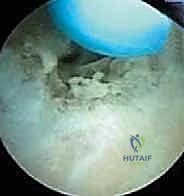

3. الاستكشاف التشخيصي بالمنظار:

يتم إدخال كاميرا المنظار عالية الدقة. يقوم الدكتور هطيف بإجراء فحص شامل وفحص ديناميكي للمفصل من الداخل، لتقييم حالة الغضاريف، البحث عن الأجسام الحرة (Loose bodies) الناتجة عن تفتت العظام، وتقييم حجم النتوءات العظمية في الناتئ المرفقي.

4. إزالة النتوءات العظمية (Osteophyte Excision):

هذه هي الخطوة الأكثر دقة وحساسية، وهنا تتجلى خبرة الأستاذ الدكتور محمد هطيف. باستخدام أدوات دقيقة (Burr)، يقوم بنحت وإزالة النتوءات العظمية الخلفية التي تسبب الانحشار.

تحذير جراحي هام: يؤكد الدكتور هطيف دائماً على قاعدة جراحية ذهبية في هذه العملية: "يجب إزالة العظام الزائدة فقط (النتوءات)، ويجب عدم المبالغة في إزالة جزء من العظم الأصلي للناتئ المرفقي". لماذا؟ لأن الإفراط في إزالة العظم سيؤدي إلى فقدان المفصل لاستقراره العظمي، مما يضع ضغطاً مضاعفاً ومميتاً على الرباط الجانبي الزندي (UCL)، وقد يؤدي إلى تمزقه بالكامل لاحقاً. هذه الدقة في تحديد "كمية العظم المزال" هي ما يميز الجراح الخبير عن غيره.